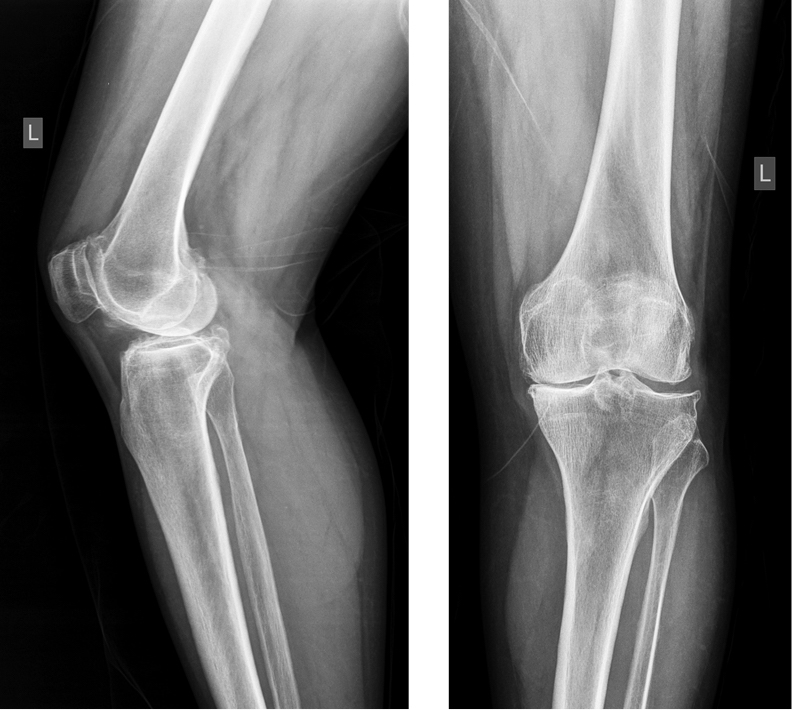

После предоперационной подготовки, выполненной согласно протоколам Центра, из стандартного срединного доступа была выполнена операция тотального эндопротезирования левого коленного сустава с имплантацией эндопротеза с сохранением задней крестообразной связки (рис. 2).

Рис. 2. Послеоперационные рентгенограммы коленного сустава пациентки, выполненные на следующий день после эндопротезирования

Fig. 2. Postoperative knee X-rays performed the day after arthroplasty